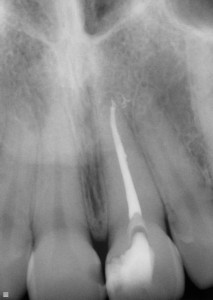

The dentist will examine the tooth and an x-ray is necessary to inspect the root for possible infection.

If root treatment has not been performed this will be the next step. This will ensure all the infection is gone and even that the tooth is now 'dead', it is still durable and strong to last many years to come.

Root treatment done

White line indicating

root treatment